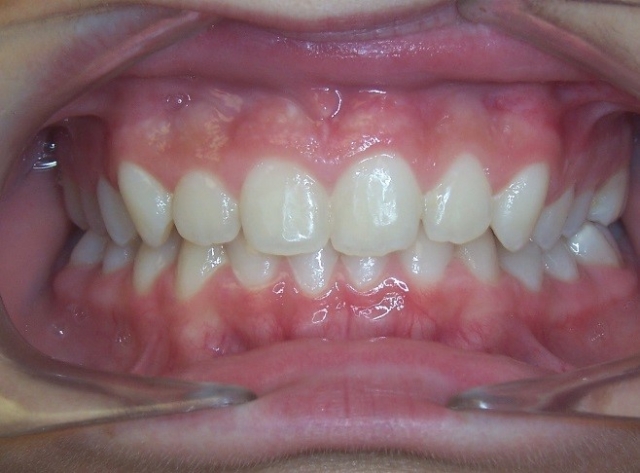

Key #1: Anatomy studies of the mid-palatal suture document that the suture becomes more complex with maturity. The suture system of younger patients is very responsive to the orthopedic intervention of the expander. This benefits the maxillary complex because less pressure is needed to achieve the desired skeletal expansion. When less pressure is used, we reduce the risks for negative consequences to the buccal bone. As a patient matures, there is a greater risk of teeth tipping with expansion and less stable orthodontic expansion rather than orthopedic expansion.

Key #2: An expander during the early mixed dentition allows the primary teeth to anchor the expansion appliance. This has significant benefits for permanent dentition that eliminate potential adverse effects, including dehiscence of the buccal bone, gingival recession, and root resorption. Expansion appliances use the strength of the roots and surrounding bone of the teeth to which they are attached. Consequently, those teeth and supporting bone carry the lateral pressure of the expansion as the suture opens. When primary teeth support the expander, the succedaneous bicuspids and canines do not bear any expansion pressure. The newly erupting teeth only benefit from the additional space development the expander has created. The acrylic bonded expander is easily constructed to adapt exclusively to the primary dentition, and has the added benefit of spreading the attachment over several teeth on each side. A banded hyrax appliance can be attached to the second primary molars and canines, or the permanent first and primary first molar. Studies have reported that using a Haas expansion appliance attached to the second primary molars and primary canines is successful and stable.

Key #4: When teeth erupt into a prepared site with adequate bone and soft tissue support, it is ideal for long-term stability and sound periodontal support. A similar protocol is followed when preparing a site with a graft for receiving an implant or grafting in an alveolar cleft site to receive the erupting canine. To prepare the space for expansion, follow the same principles for site preparation. In a crowded developing dentition, the plan to develop eruption space will decrease the risk of ectopic eruption with a compromised gingival attachment